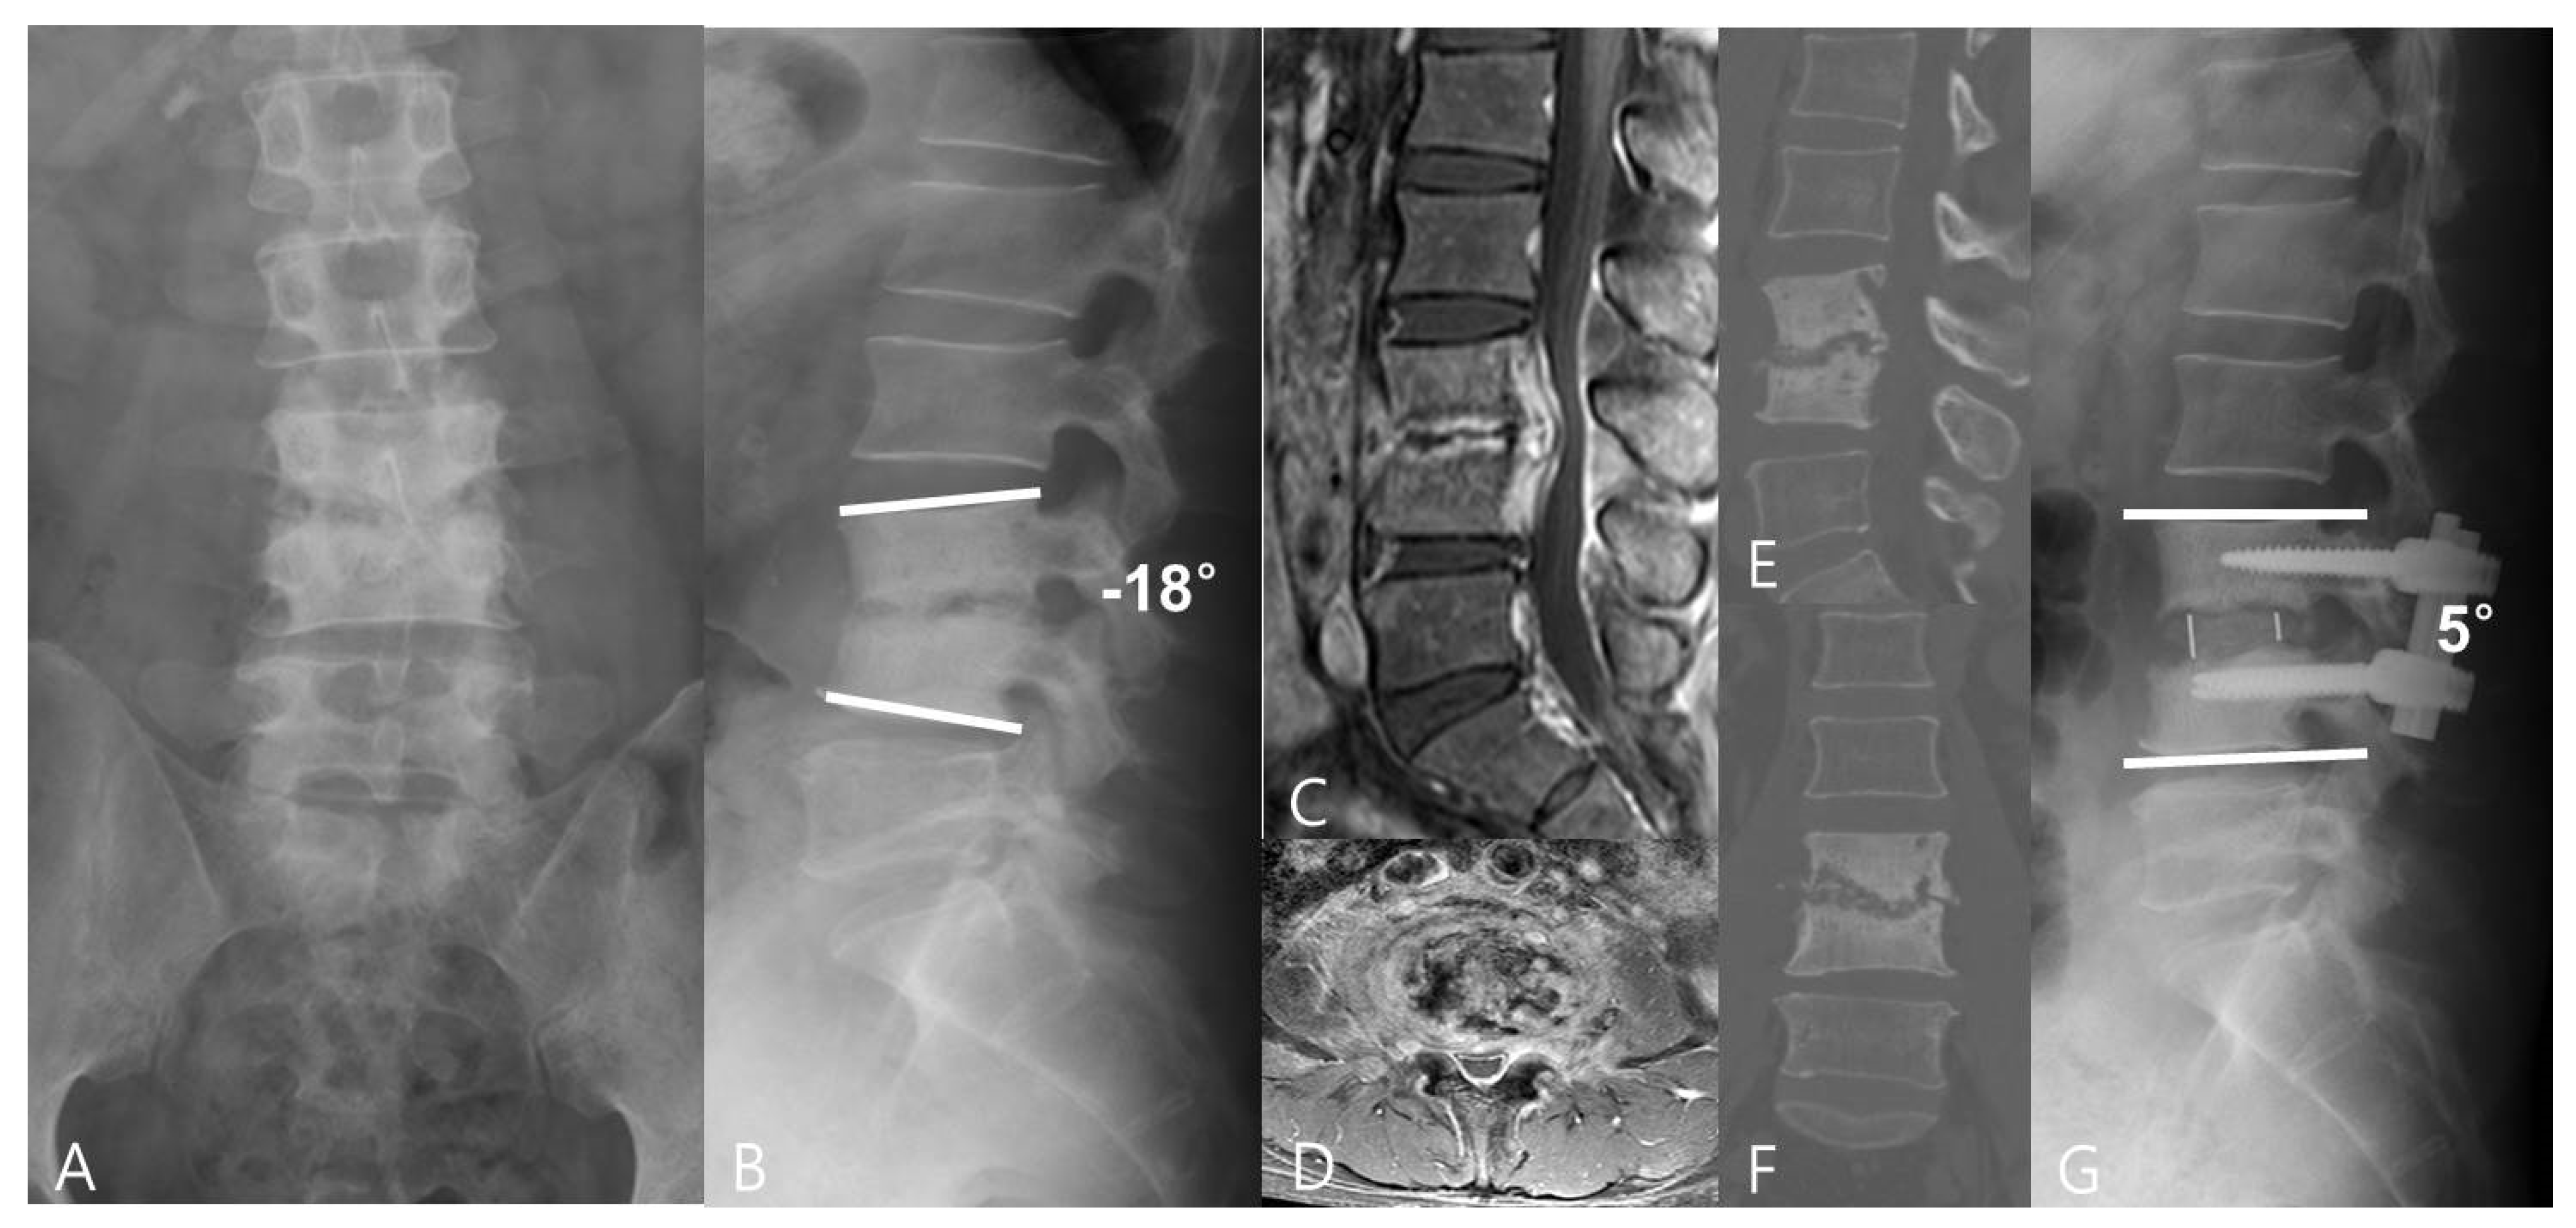

Figure 1.

A 44−year−old man had lower back pain for more than 2 months. (A,B) The preoperative anteroposterior and lateral radiographs showed L3/4 intervertebral space narrowing and regional kyphosis. (C,D) Preoperative CT and (E,F) MRI images revealed L3/4 pyogenic spondylodiscitis with endplate destruction. A minimally invasive oblique lumbar interbody fusion using PEEK cages with an autologous bone graft was performed. (G) Plain lateral radiographs at the last follow-up showed L3/4 interbody fusion and good correction of regional kyphosis.

The intraobserver agreement rate was 96% (mean k = 0.83) and interobserver agreement rate was 93% (mean k = 0.77); good agreement was presented. The radiographic outcome measures are presented in Table 2. The pre-operative LL, RL, PI, and PT of both groups were similar. The postoperative and final follow-up LL, RL, and DH were improved in both groups (p < 0.001) (Figure 1 and Figure 2). The improvements of LL of both groups were not statistical different, but the improvement of RL and DH for the OLIF group was better than that found for the ALIF group (p < 0.001). At the final follow-up, although the LL and RL of both groups had decreased slightly, the data were not statistically significant for either group.